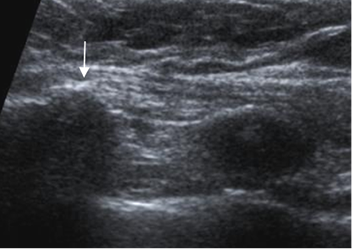

Fig 33 A. Costocondritis.

Ecografía. Lado izquierdo normal. En el lado derecho hay prominencia de la articulación condroesternal, con formación de osteofitos (Flecha), por cambios degenerativos.

Fig 33 B. Costocondritis.

Ecografía. Cambios inflamatorios en la unión condroesternal derecha, con escaso líquido.